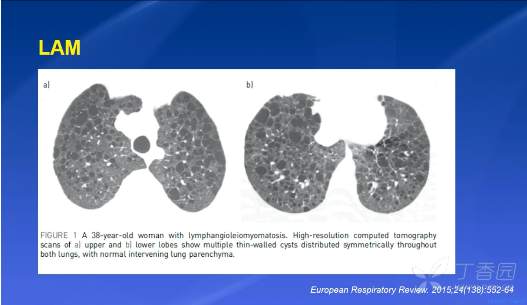

LAM 淋巴管肌瘤病